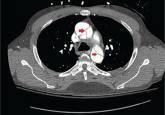

ArticleAortic dissection presenting as ischemic limbAuthor:Faiza Khalid, MDPublish date: June 1, 2018With surgical repair and blood pressure control, the patient recovered and left the hospital 1 week later.Read More